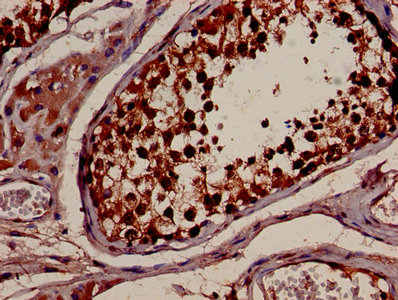

• IHC image of CSB-PA01544A0Rb diluted at 1:600 and staining in paraffin-embedded human kidney tissue performed on a Leica BondTM system. After dewaxing and hydration, antigen retrieval was mediated by high pressure in a citrate buffer (pH 6.0). Section was blocked with 10% normal goat serum 30min at RT. Then primary antibody (1% BSA) was incubated at 4°C overnight. The primary is detected by a biotinylated secondary antibody and visualized using an HRP conjugated SP system.

• IHC image of CSB-PA01544A0Rb diluted at 1:600 and staining in paraffin-embedded human testis tissue performed on a Leica BondTM system. After dewaxing and hydration, antigen retrieval was mediated by high pressure in a citrate buffer (pH 6.0). Section was blocked with 10% normal goat serum 30min at RT. Then primary antibody (1% BSA) was incubated at 4°C overnight. The primary is detected by a biotinylated secondary antibody and visualized using an HRP conjugated SP system.